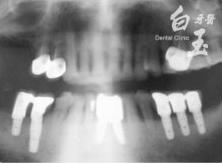

患者全口 X 光

治療後